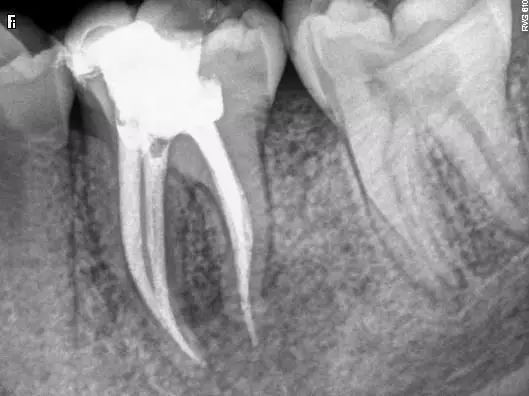

4)根管欠填或超填 良好的根管充填是适填,无论是去髓术或根管治疗,只要根管经过有效的药物消毒,允许少量欠填或超填(0.5~1.0㎜)。但如欠填过多,近根尖孔处形成死腔,可能导致组织液滞留,尤其是根尖周有炎症者,带有细菌的液体回流积聚,可继续成为感染源,使根尖周病变难以愈合。而超填过多的牙胶尖难以被组织吸收,同样会影响病变的愈合。